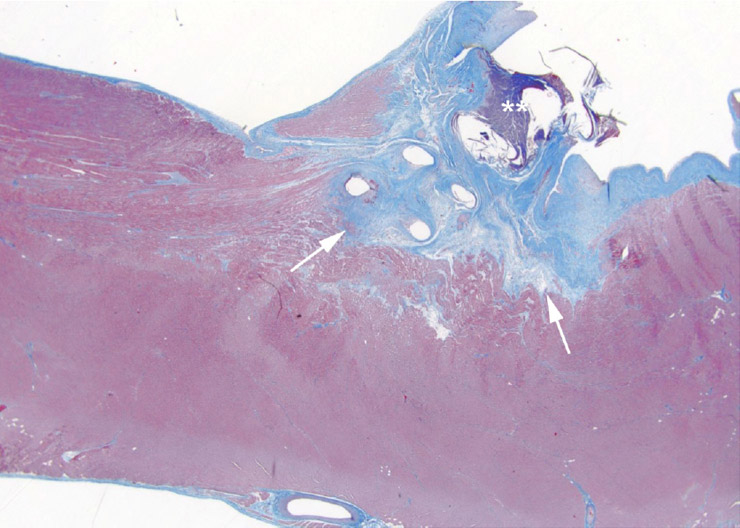

Figure 1

Histological specimen of the heart muscle obtained in a pig with implanted conventional pacemaker lead after imaging with a high power RF MRI scan. Tissue damage due to heating around the lead tip is visible (arrow). Note: The location of the lead tip is highlighted by asterisks.

The most important risk posed by MR imaging in patients with pacemakers is a transient or permanent influence or definite damage to the electric components of the pacemaker device (i.e., activation of the reed-switch, pacemaker resets of reprogramming). This interaction may lead to asynchronous or unpredictable pacing, which may result in tachycardia or asystole [9]. Also, animal testing has demonstrated that the temperature at the lead tip increased up to 20 °C during MRI scanning of the heart, thus possibly resulting in tissue damage [10] (fig. 1). The risk of pacemaker displacement by a possible interaction with the static magnetic field is considered to be of minor importance. Another disadvantage of conventional pacemakers is the fact that the device and the leads produce metallic artifacts which may hamper imaging interpretation at the level of the heart and the mediastinum. First experience with MRI SureScan devices did indicate that the artifacts induced by the leads and the device itself may not limit the MR scan’s diagnostic value (fig. 2).